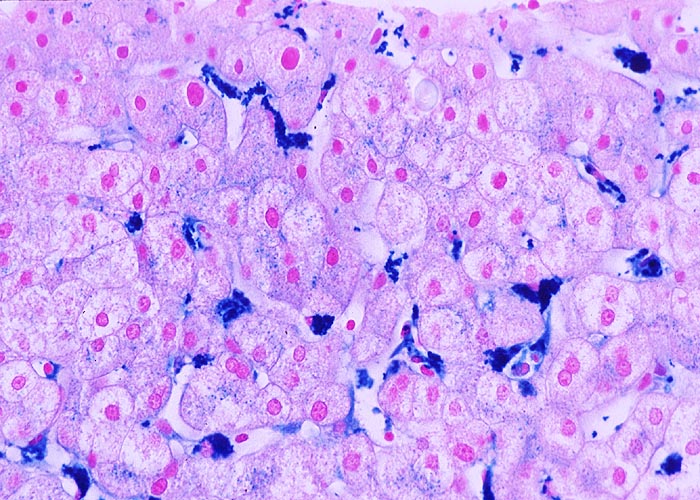

PathoPic – image database / PathoPic ID 975 - Sternzellsiderose

Sternzellsiderose

Artefakt / Fremdkörper / Pigment

Leber

In der Eisenfärbung werden die Hämosiderin speichernden Kupffer'schen Sternzellen in den Sinusoiden gut sichtbar. In den Hepatozyten finden sich nur sehr geringe feinkörnige Eisenpigmentablagerungen.

Zahlreiche Bluttransfusionen wegen hämatologischer Erkrankung.